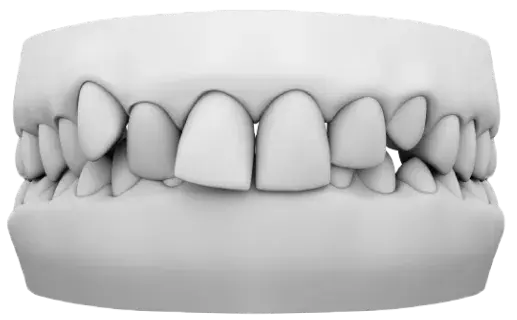

Crowding